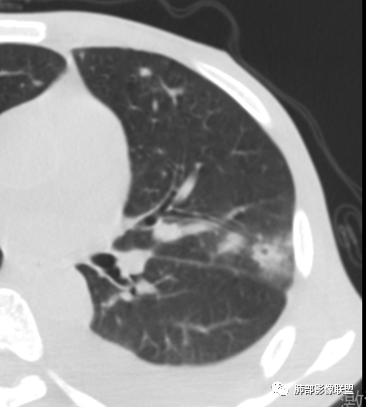

单看这2比较附图,像是真菌

2.双肺散在不规则小片状影及结节影,部分可见磨玻璃晕。结节影边界较清楚。左肺片影边界不清,范围较大,支气管相关,支气管壁增厚不明显,病灶内见液化空洞。

3.肺炎型肺部影像学表现常为双肺多发片影,肉芽肿样结节影,边界相对清楚,可见磨玻璃晕,部分病灶可显示坏死空洞。部分病例出现胸水。支气管炎型病例可见较广泛支气管壁增厚。

单就肺部影像学表现而言,有时与其他一些真菌感染如曲霉病并不好区分。